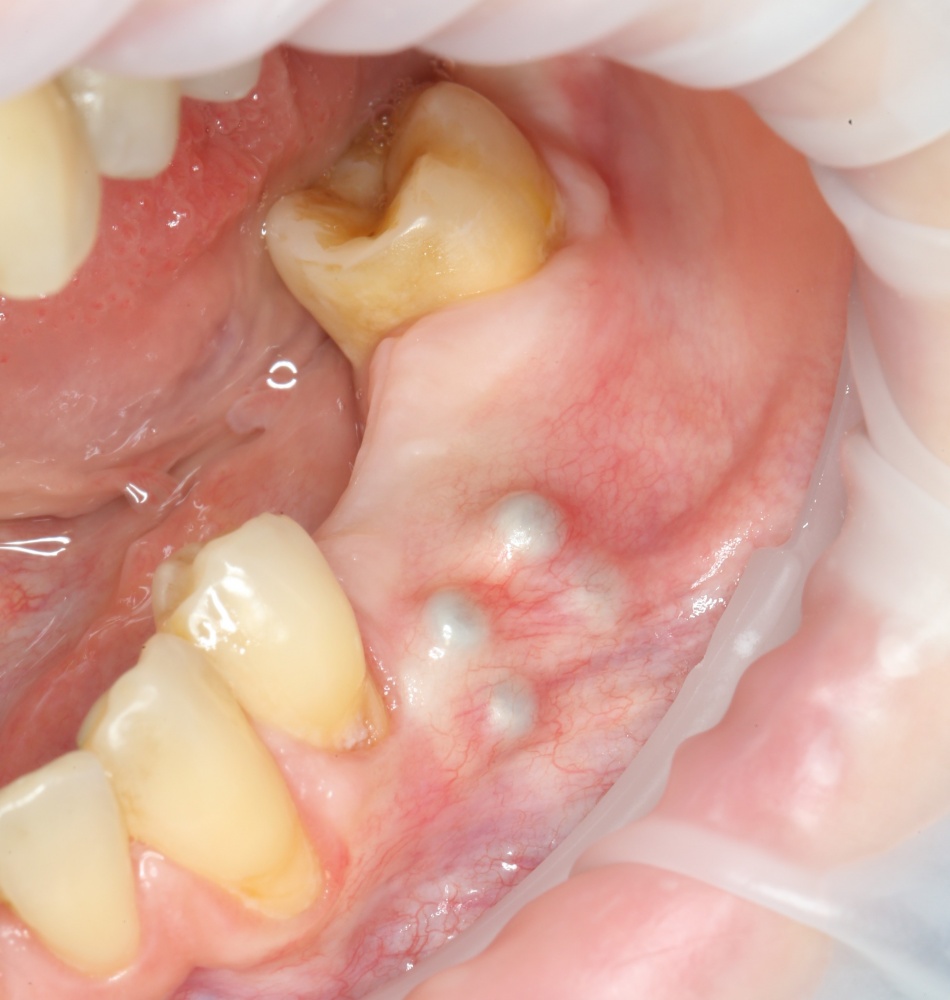

Например, вот клиническая ситуация:

A09A4758 (2)

Можем ли мы установить импланты в этом случае? «Вкрутить» — да, сможем. Установить в правильное положение, обеспечить качественное и долговечное протезирование — нет, вряд ли. Поэтому в данном случае лучше разбить лечение на несколько этапов. Сначала остеопластика:

A09A4769 (2)

Потом, через 3 месяца, установка правильных имплантов в правильное положение:

A09A1787 (2)